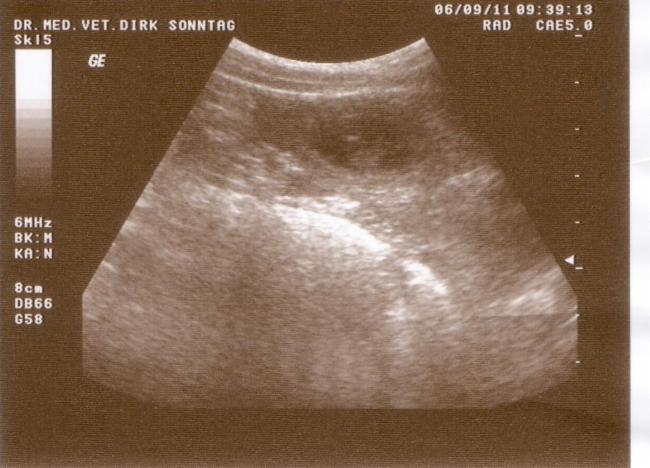

06.09.2011 Die Ultraschalluntersuchung

Der 26. Tag der Trächtigkeit war auch der Tag der Ultraschalluntersuchung. Er zeigte was ich schon lange wusste: Elena trägt die B-chen in sich. 10 Welpen konnten wir auf Anhieb entdecken. Wie viele es wirklich werden, wird Elena erst Mitte Oktober veraten, doch wer sich an den Ultraschall des A-Wurfes erinnert, kann sich denken das sich da vermutlich noch mehr B-chen in Elenas Bauch versteckt haben.

Stellvertretend für die anderen B-chen stellen wir hier schon mal die ersten vor: